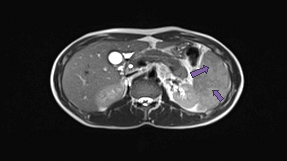

Further imaging by MRI Abdomen showed Bulky spleen demonstrating lobulated and nodular outline with multiple intra parenchymal focal lesions of variable size and many of them appears conglomerate and ill-defined identified throughout the spleen. These lesions are predominantly hypointense in T1 and T2-WI with faint areas of high T2 signal and heterogeneous enhancement. Multiple subcentimetric and/or borderline size lymph nodes are identified at the left para-aortic region, portahepatis, posterior to the gastric fundus and left anterior supradiaphragmatic region the largest measuring 10 mm in short axis (left para-aortic) at SMA level (Figure 2).

Figure 2 Axial T2 and multi-planer contrast enhanced T1 Fat suppressed images of the abdomen showing a bulky spleen demonstrating a lobulated outline with multiple conglomerated intra parenchymal focal lesions of variable sizes showing predominantly hypo-intense signal on T1 and T2-WI with faint areas of heterogeneous enhancement.